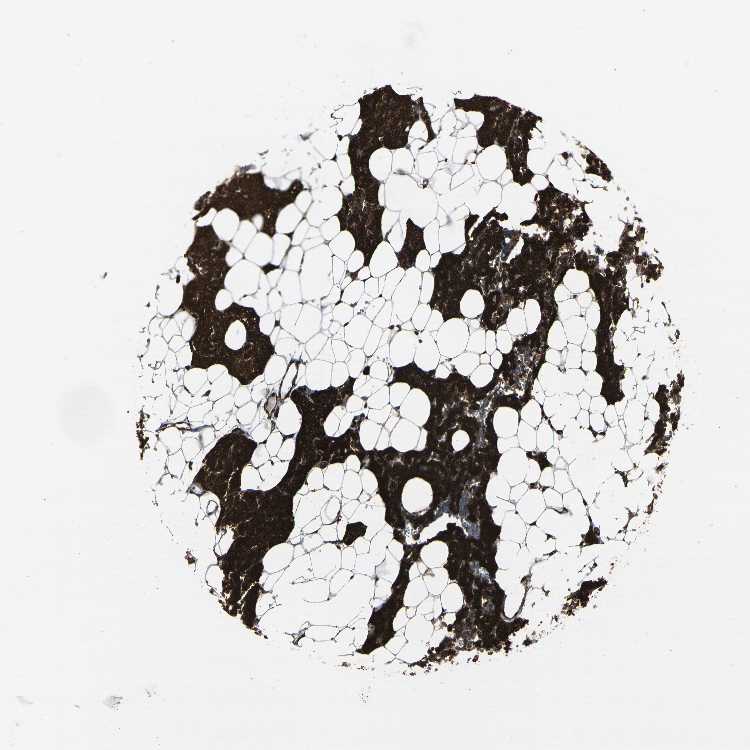

PARATHYROID GLAND - Antibody stainingi

Antibody staining in the annotated cell types in the current human tissue is reported as not detected, low, medium, or high, based on conventional immunohistochemistry profiling in selected tissues. This score is based on the combination of the staining intensity and fraction of stained cells.

Each image is clickable and will lead to virtual microscopy that enables deeper exploration of all samples and also displays staining intensity scores, fraction scores and subcellular localization as well as patient and tissue information for each sample.

Antibody HPA014063

Glandular cells High